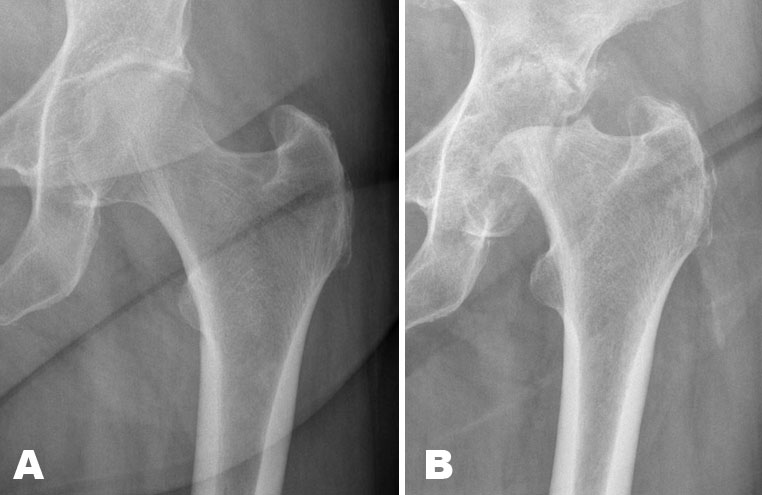

A 75-year-old woman presented with an increasingly painful left hip over a few months. Before one year she had been diagnosed with mild coxarthrosis (Figure 1A). She had otherwise no medical history. At clinical examination, she had a leg discrepancy of 2 cm and reported pain in all active and passive motions.

The radiographs showed complete destruction of the left femoral head with a hatchet-like deformity, and cortical irregularities and defects in the acetabulum confirmed by computed tomography (CT) (Figure 1B).

Figure 1: (A) The initial radiography of the left hip one year previously shows only mild reduction of the joint space. (B) Radiograph shows complete destruction of the femoral head with a hatchet-like deformity and cortical irregularities of the acetabulum.

The etiology of rapid destructive osteoarthritis of the hip is still unclear. It is associated with rapid chondrolysis and poor bone response. Subchondral fractures in the femoral head may be part of the etiopathogenesis [2],[4],[5]. Initially, radiographs and CT may demonstrate either normal findings or mild osteoarthritis, but with lack of osteophytes. Over the next months there is progressively subchondral bone loss in the femoral head and acetabulum with finally complete destruction of the femoral head, often described as a hatchet-like deformity on radiography and CT with a sharp margin also presents in this case (Figure 1B). Key MRI features are bone marrow edema, joint effusion, synovitis, and subchondral cyst-like lesions. Subchondral fracture lines are characterized by a band of low signal intensity on all sequences paralleling the articular surface, which may overlap the radiological appearance of primary osteonecrosis, although considered a different entity [1].

The radiologic features of rapid destructive osteoarthritis overlap other destructive arthropathies, and the clinical history is therefore essential. The atrophic form of Charcot arthropathy is also characterized by bone resorption, joint destruction, and absence of osteophytes, but is painless [9],[10]. There was no evidence of diabetic or other neuropathy causing sensorineural deficit in this patient. The hatch-like, sharp margin of the femoral neck (Figure 1B) and the lack of soft-tissue component on MRI made the diagnosis of malignant osteolysis improbable. There was no anamnestic trauma as in massive osteolysis of the femoral head (MOFH) following acetabular fractures [11]. There have been several reports of rapid destructive osteoarthritis in association with rheumatoid arthritis, but in this case there were no clinical or laboratory findings supportive of inflammatory genesis [12]. Crystal deposition disease can be excluded by aspiration of crystal-free joint fluid [13]. Gorham’s disease, also known as vanishing bone disease, is a very rare disorder characterized by osteolysis and angiomatous proliferation generally affecting persons younger than 40 years old. In this disorder radiography, initially show radiolucent foci in the intramedullary or subcortical regions of the affected bone, and later disappearance of bone with tapering of the remaining osseous tissue [14].